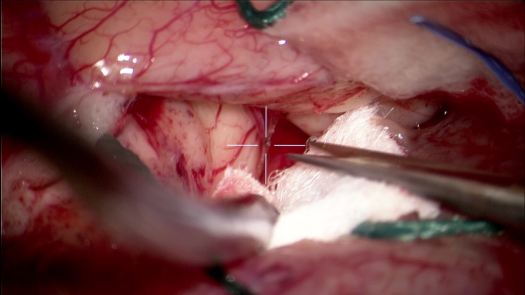

Resezione microchirurgica di tumore cerebrale (glioma alto grado cortico-sottocorticale) frontale dx